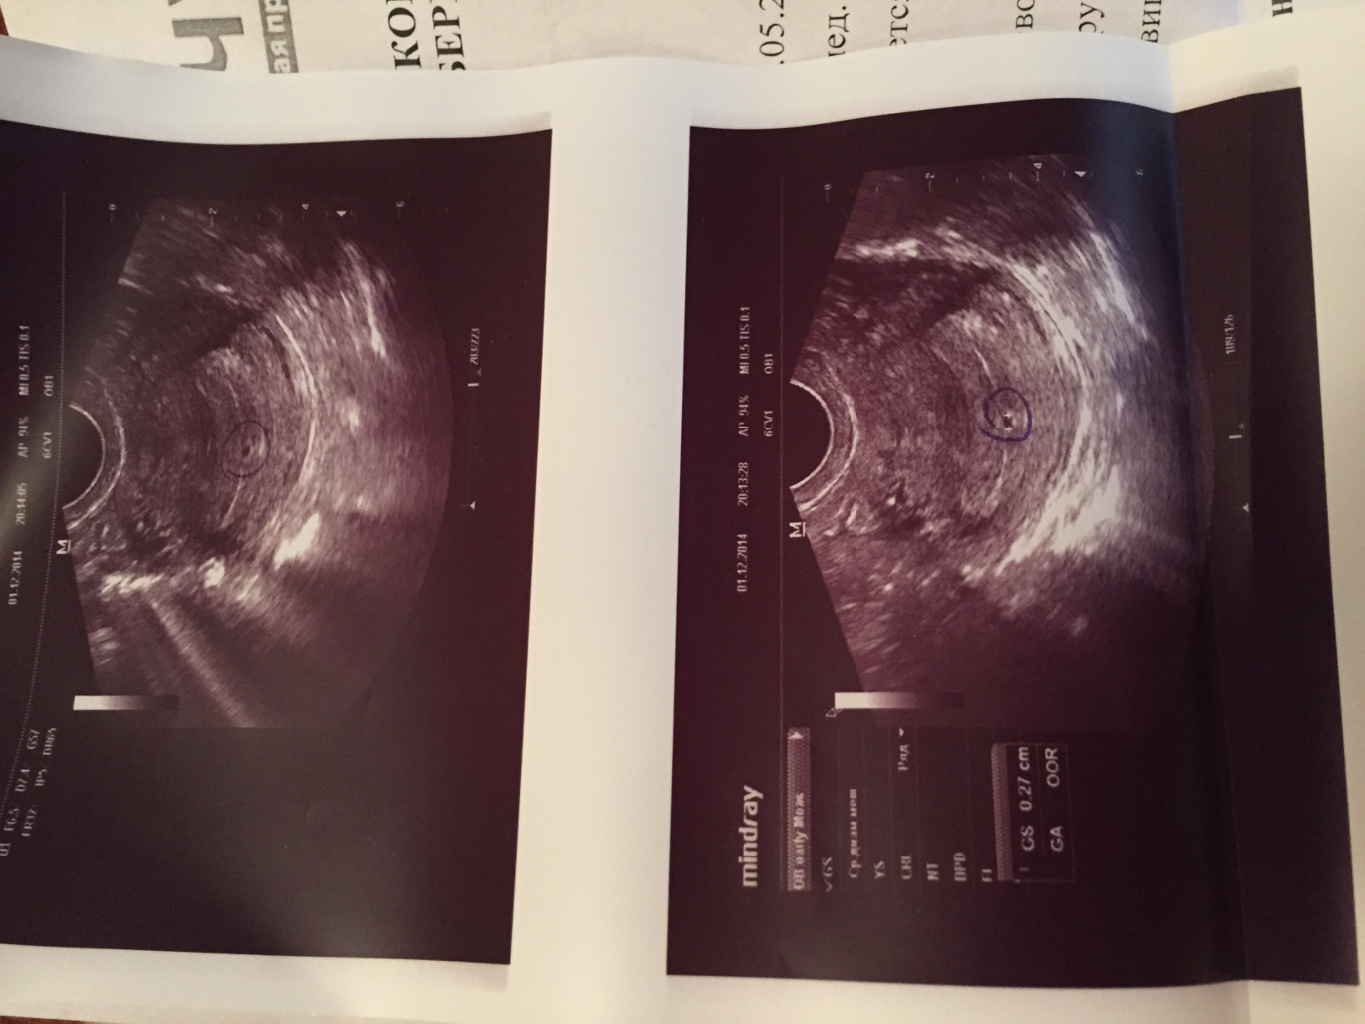

Как выглядит ребенок на узи фото в 10 недель?

На этой стадии беременности ребенок становится все более осознанным и активным. Узи фотографии показывают, что его плодовой мешок становится уже образованным, а сердцебиение можно услышать с помощью узи аппарата.

Узи фотографии на 10 неделе беременности позволяют врачу и родителям отслеживать развитие ребенка и убедиться в его здоровье. Кроме того, они могут стать прекрасным сувениром для будущих родителей, чтобы сохранить воспоминания о начале этого незабываемого путешествия.